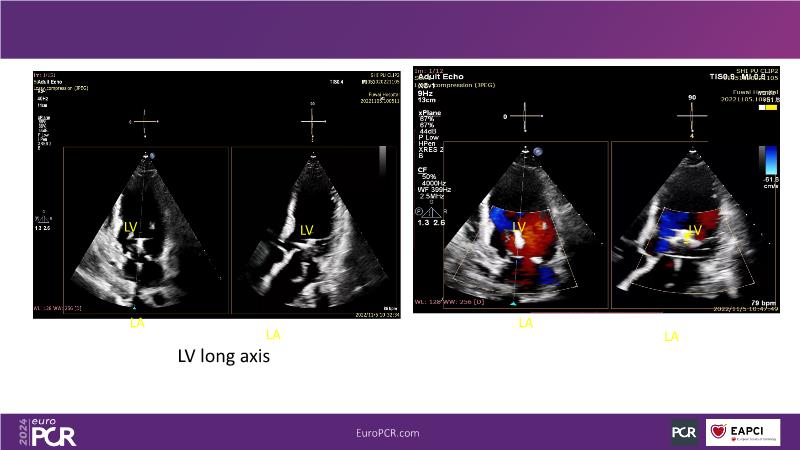

Watch this session to gain insights into the clinical evidence of mitral TEER therapy for the Asian population, learn techniques for implanting a MitraClip in patients with challenging anatomy, and understand how to use the four clip sizes for optimal outcomes. The session also covers educational aspects of clipping in dextrocardia, the benefits of reserve bending of the transseptal needle for tenting and puncture, new steering maneuvers for dextrocardia patients, and the importance of understanding anatomy and collaborating closely with the echo team for success.